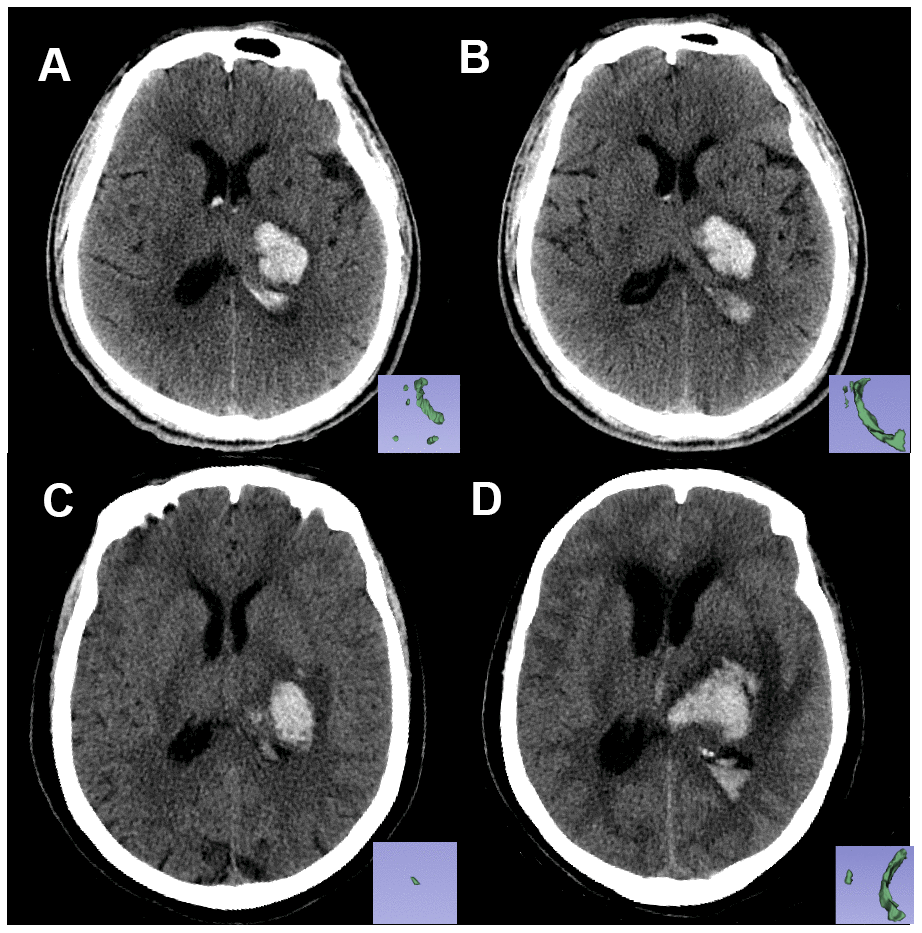

Among the seven radiomics features used to construct the Rad-score, features from group GLZSM characterized the texture homogeneity of lesions, and the Feature Haralick Correlation from group GLCM measured the degree of image gray level similarity. Previous reports indicated that hematoma heterogeneity was a sign of active bleeding and could predict hematoma development [10, 12]. We inferred that the radiomics features captured the intrahematomal heterogeneity. Nevertheless, interpreting the association between the radiomics features and the underlying biological processes is challenging. The Rad-score incorporates multiple radiomics features and serves as a multi-factor panel that reduces the complexity of multi-feature studies [13]. For example, the Rad-score could differentiate between similar hematomas in two patients and specify their different outcomes (Figure 4).

Figure 4. Non-contrast CT images of two patients with similar hematoma but different experiences. Pictures in the lower right corner are the 3-D images of the IVH. Image (A, B) are the baseline and follow-up CT images, respectively, of patient A: a 61-year-old male who had a Rad-score of -2.2119681 (<-1.7259179). Image (C, D) are the baseline and follow-up CT images, respectively, of patient B: a 67-year-old female with a Rad-score of -1.6176548 (>-1.7259179). Within 24 hours from symptom onset, the IVH volume of patient A changed from 5.62 mL to 6.84 mL, and the IVH volume of patient B changed from 0.5 mL to 12.4 mL. Patient B experienced IVH growth while patient A did not.